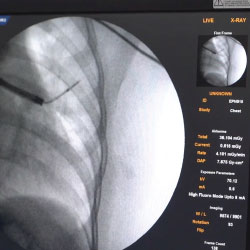

Cone Beam CT – Basics |

15 |

- All Courses Include Live cases in the Operating Room along with Participants Simulation

- Didactics, SiM Lab and Live Cases in the Operating room